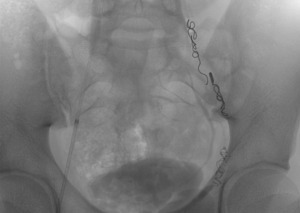

Оперативное вмешательство проводится под рентгеновским контролем.- Путем прокола в бедренной вене в организм вводится катетер, поставляющий в яичковую вену склерозирующее лекарство, закупоривающее яичковую вену.

- Одна из наименее эффективных операций – после нее существует большая огромная вероятность проявления рецидива.

- склеротизация, эмболизация. Ключевым отличием является закупоривание вены при помощи особых веществ: склерозанты, спирали, скобы из титана и т. п. Преимущества: проводится под местным обезболивающим, безболезненное лечение, риск рецидива 7%, отсутствие осложнений после операции, минимальный период реабилитации. Недостатки: дороговизна, необходимость в специальном оборудовании и специфических навыках хирурга, а также облучение рентгеном;